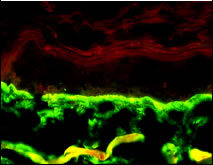

Ein Wirkstoff auf Malzbasis, Basaline , ist in der Lage, als 2%ige Creme viermalig über 10 Tage topisch angewendet, die Lamininsynthese in der Basalmembran des Hautmodells zu stimulieren (Abb. 6).

Abb. 6: Immunfluoreszenz-Färbung von Laminin in der Basalmembran des Ganzhautmodells nach viermaliger Behandlung mit 2%iger Basaline -Creme über 10 Tage.

Placebocreme:

|

Basaline-Creme:

|